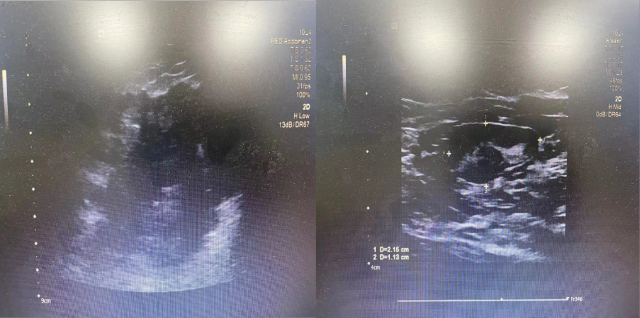

乳腺彩超显示: 右乳可见大小约 9.0×7.8×6.8cm 的低回声结节,边界不清,外形不规则,右腋下可见 2.2×1.1cm 大小淋巴结,边界清,形态规则。检查诊断:右乳低回声结节,考虑:BI-RADS 5 级;双侧腋下低回声结节,考虑:淋巴结(右侧肿大)。